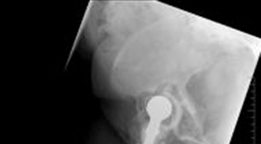

A highly porous metal cup is then impacted into the defect. The cup is often placed in an off-axis orientation, prioritizing host bone contact and initial stability over anatomic version and inclination. The subsequent cementation of the liner into the cage will correct the final articular geometry. If large cavitary defects remain behind the cup, highly porous metal augments or impacted cancellous allograft are utilized to fill the voids and support the primary shell. Multiple multi-hole screws are placed through the cup into the superior dome and posterior column to maximize initial fixation.

The cage is inserted by first seating the inferior flange into the ischium. The superior flange is then impacted against the ilium. The cage should sit intimately against the previously placed highly porous cup. Fixation begins with the placement of cortical or cancellous screws through the superior flange into the dense bone of the ilium, aiming toward the sacroiliac joint. Screws are also placed through the central dome of the cage, passing through the cage, the underlying porous cup, and into the host bone, effectively locking the two components together. Care must be taken to avoid the superior gluteal neurovascular bundle during superior flange screw placement and the external iliac vessels during anterior screw placement.

Liner Cementation and Final Reduction

The liner is pressurized into the cement mantle. The critical advantage of this technique is that the surgeon can manipulate the version and inclination of the polyethylene liner independently of the orientation of the underlying cage and cup. The liner is held in optimal anatomic orientation (typically 15 to 20 degrees of anteversion and 40 to 45 degrees of inclination) until the cement fully cures. Excess cement is meticulously removed to prevent third-body wear. The femoral component is then reconstructed as dictated by the femoral defect, and the hip is reduced and assessed for stability through a full range of motion.